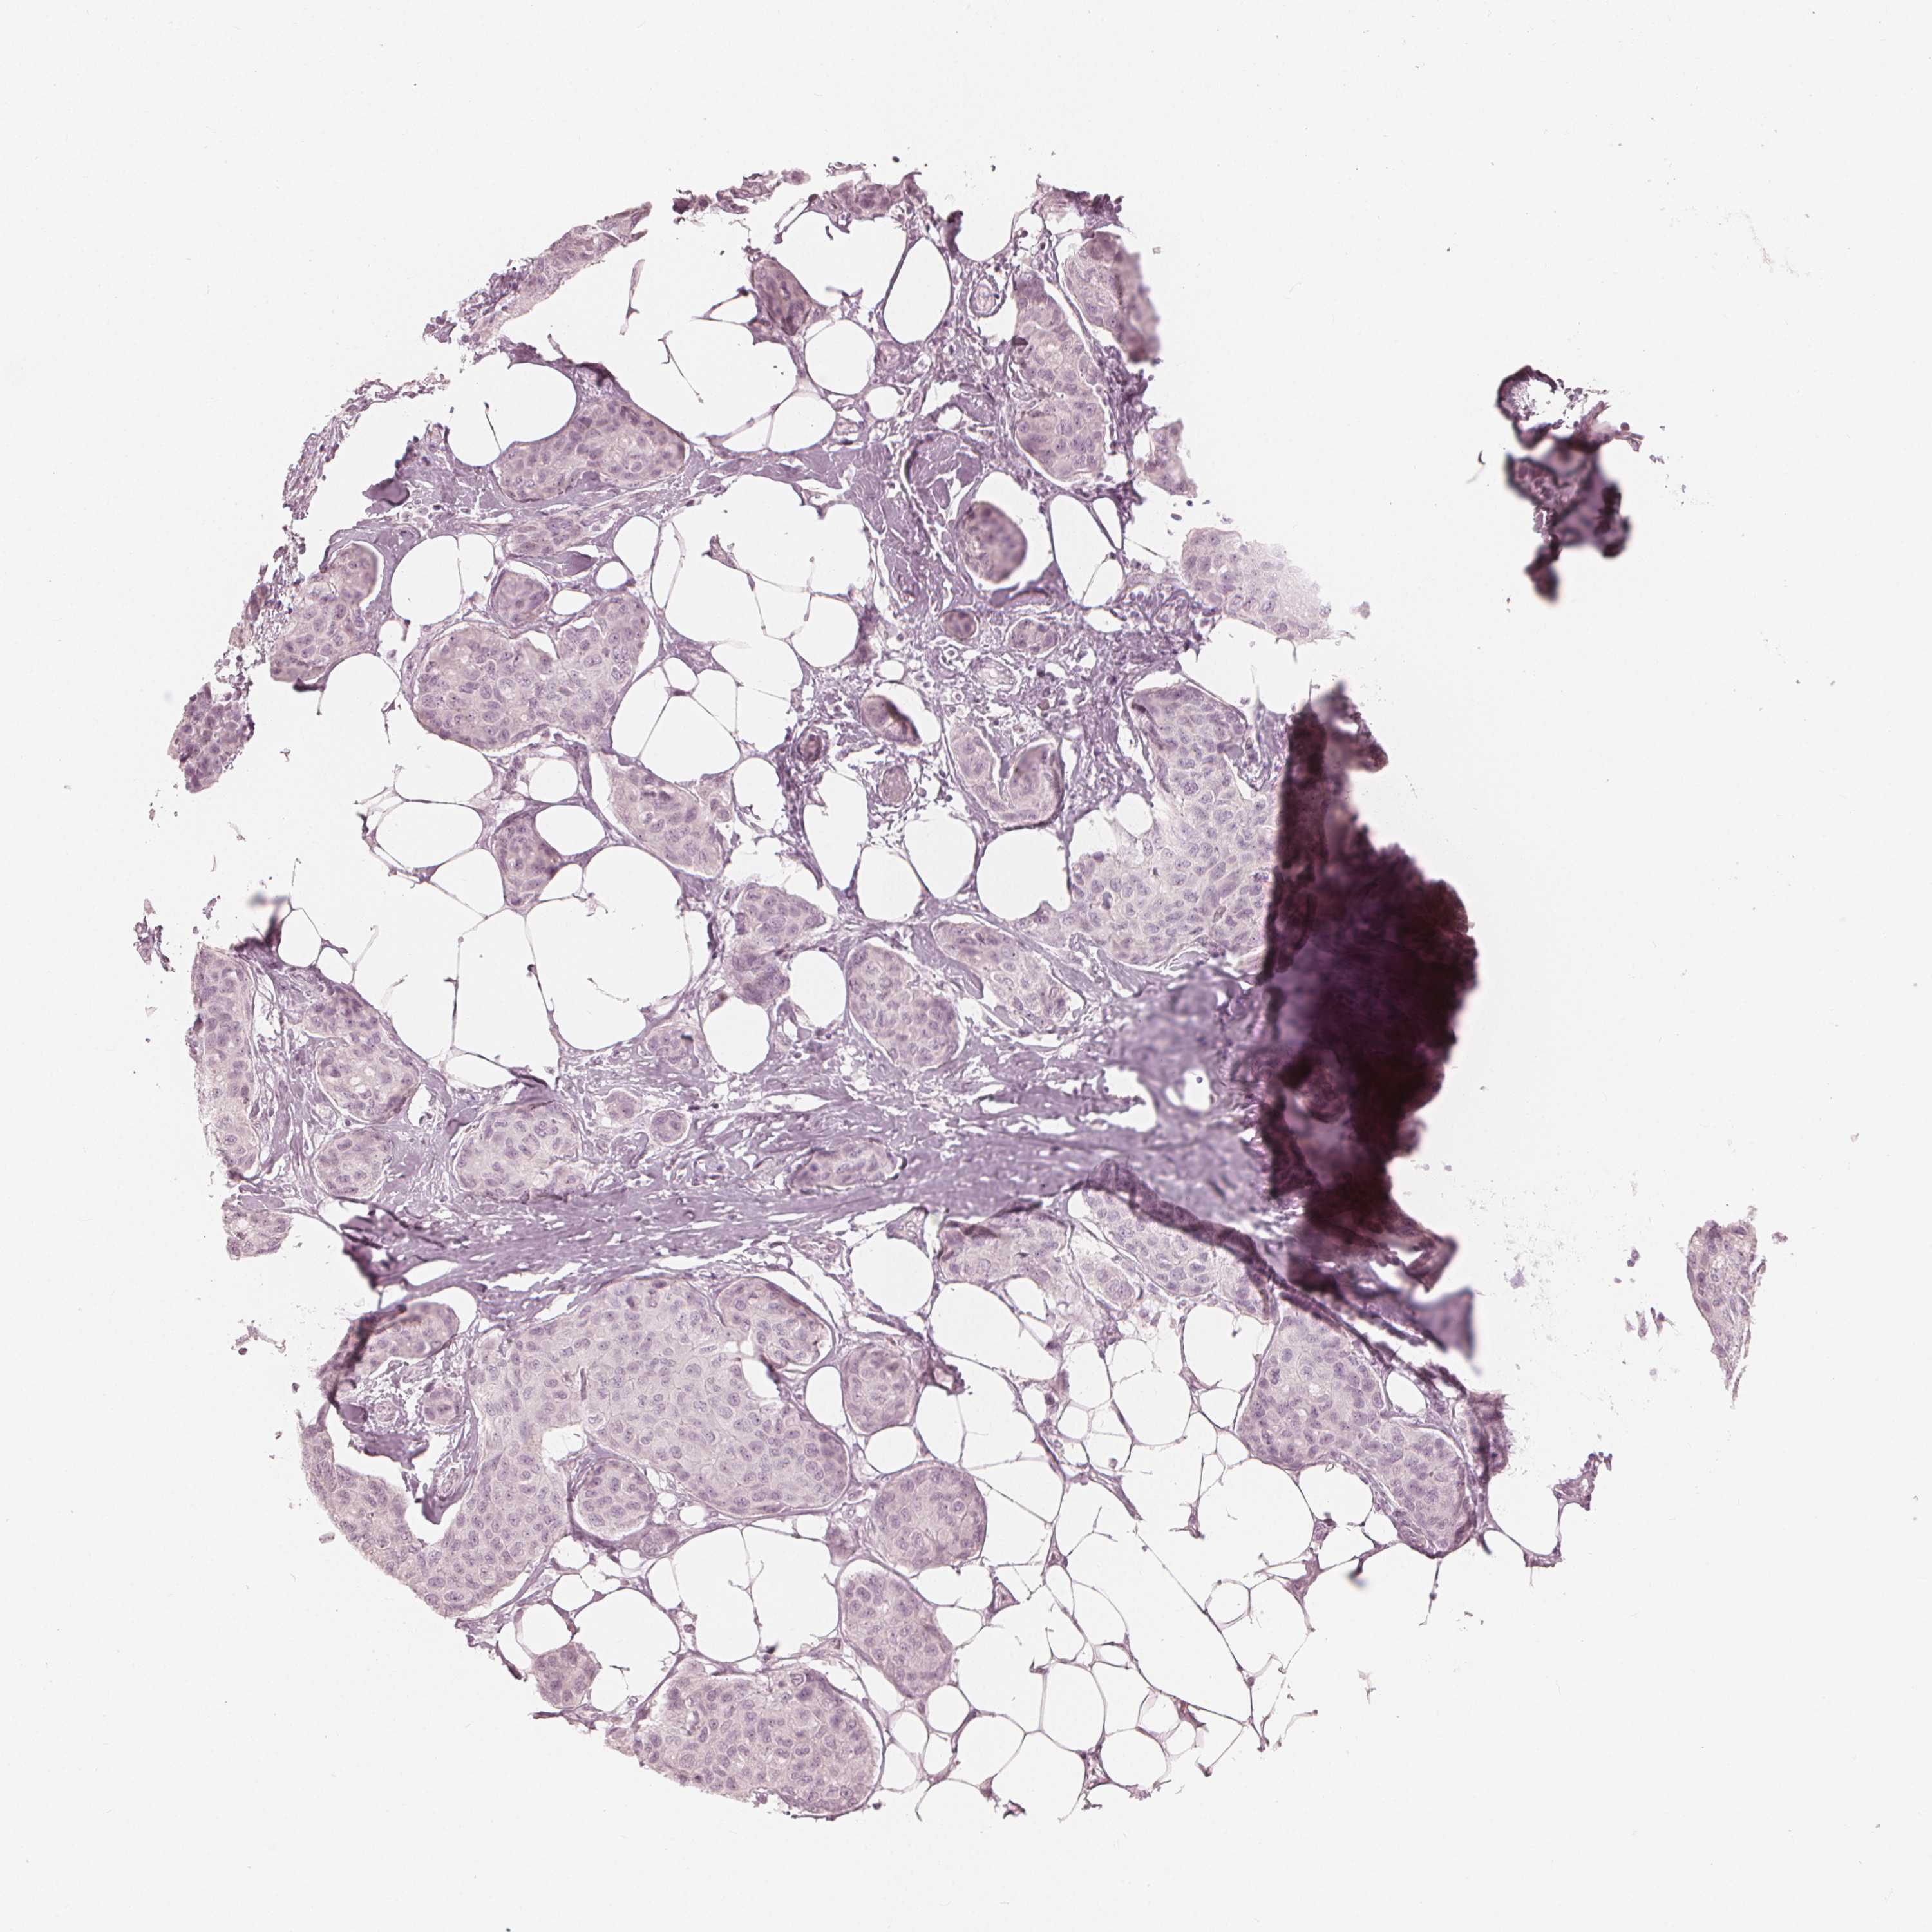

Breast cancer

Human cancer